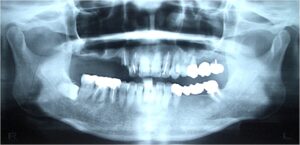

ケース2:上下に多くの問題があった70代後半男性

この方は虫歯や歯周病で残存歯が少なく、グラグラの歯が多い状態でした。最初は保険のクラスプ義歯を入れていたものの安定せず、硬いものを噛めないため外していることが多かったそうです。外見を重視してナイロン義歯を試されましたが、期待したような咬合回復は得られず、全体の再治療を希望して来院されました。

まず全顎の虫歯と歯周病の治療を行い、上顎は残存歯すべてに内冠をかぶせて連結し、全体を支えるテレスコープ義歯を製作しました。装着後は「入れ歯」というよりは取り外し可能な長いブリッジの感覚で、違和感がほとんどないとのことです。

このケースは「残った歯をチーム化して守る」発想が有効であった例です。